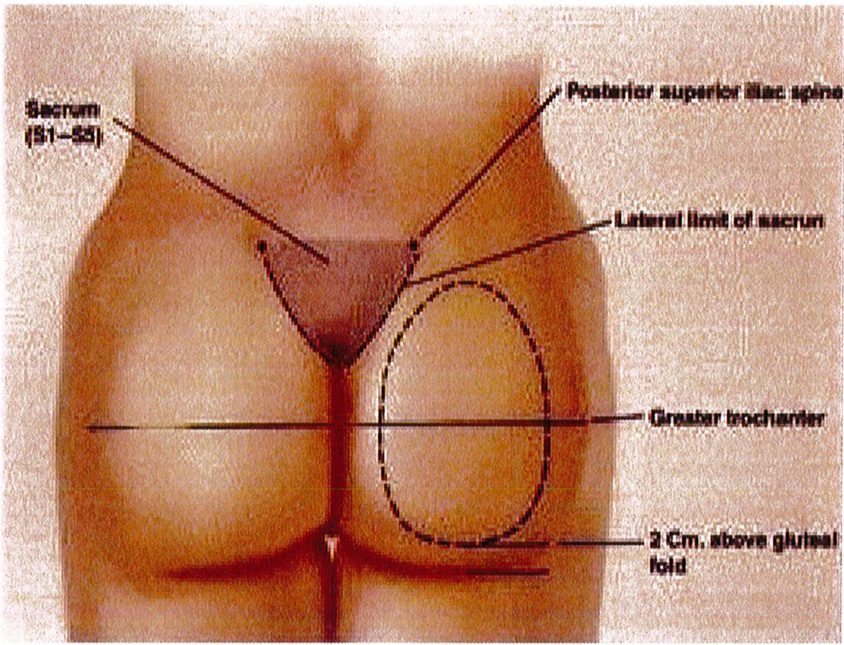

Những vấn đề mà chúng tôi đề cập trong kỹ thuật nâng mông dưới cân bao gồm các mốc giải phẫu được đánh dấu trên da trước phẫu thuật, kích thước và chất liệu khối implant.

tiêu bản như hình 4. Tiêu bản này phải được đặt chính giữa vùng mông, cách nếp lằn mông ít nhất 5cm và đường liên gai ít nhất 2cm (Hình. 5).

Bệnh nhân ở tư thế đứng, đánh dấu vị trí khối implant theo

Hình. 5. Đánh dấu vùng phẫu thuật phải tuân theo hình thể giải phẫu vốn có của từng bệnh nhân và đảm bảo rằng khối implant sẽ nằm phía ngoài xương cùng và cách nếp lằn mông khoảng 2-5 cm. (Trích từ de la Pena JA, Rubio OV, Cano JP, et al. Subfascial Gluteal Augmentation. Clin Plast Surg 2006;33:410; đã xin phép trước khi đăng tải.)